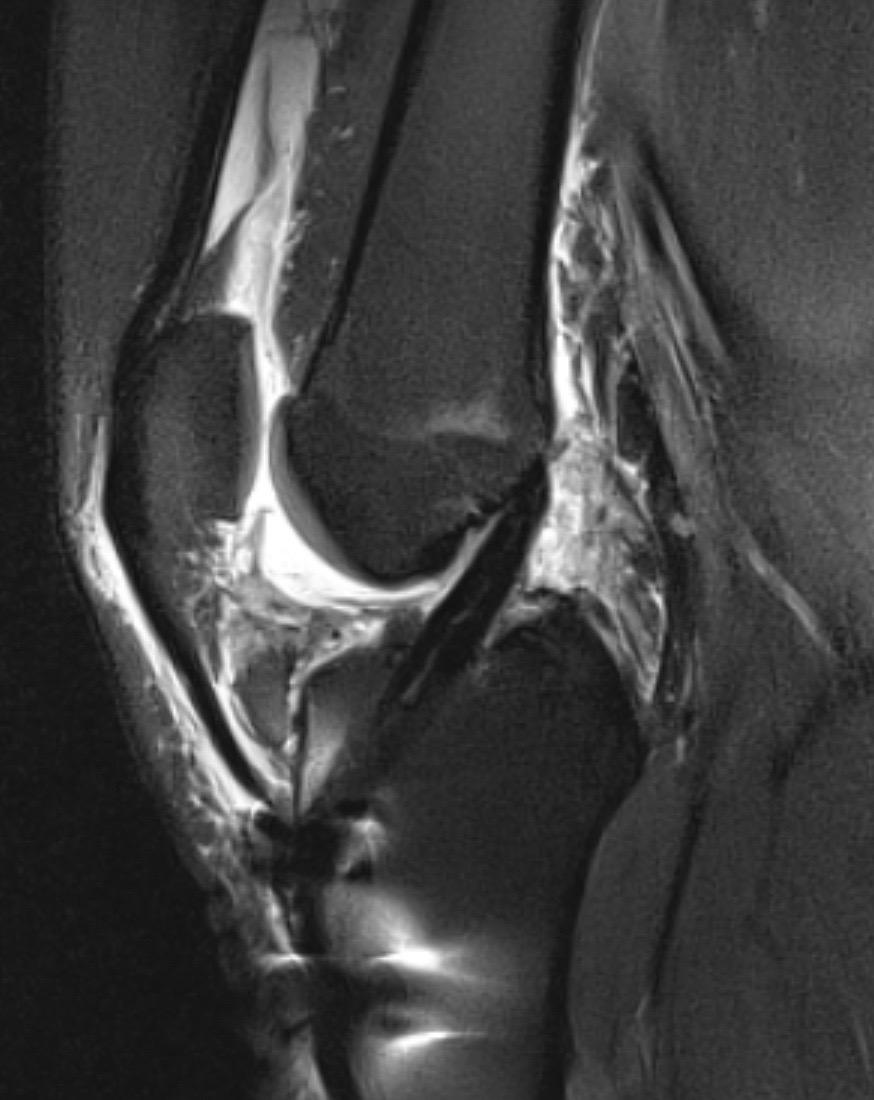

前交叉韧带重建。前叉重建+半月板修复,祝他早日康复!